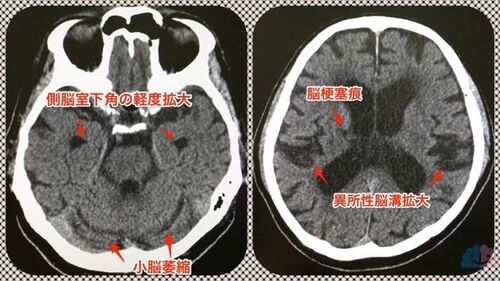

元のお父さんに戻った!

認知症外来をやっていると、時に「以前の母(父)に戻りました」という言葉を頂く。 改善例は多く経験してきたが、元に戻ったという評価はそうそう頂けないので、そう言われたときの嬉しさはひとしおである。